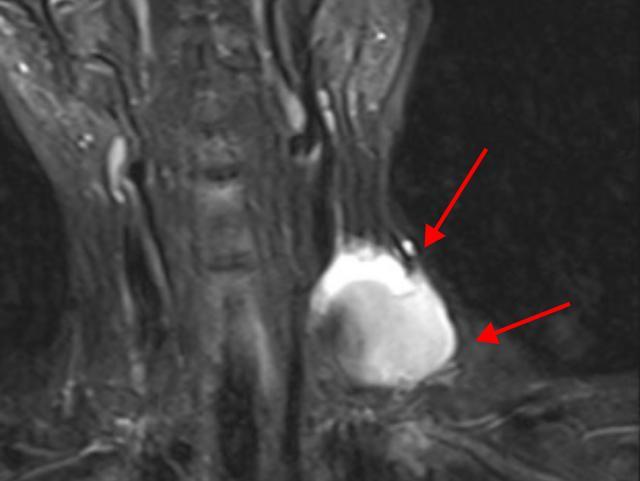

去年正月期间,文女士觉得脖子不太舒服,就让自己丈夫帮忙进行颈部按摩来放松一下,可第二天发现左侧的颈部鼓了一个包,在当地医院检查后发现是 左颈内静脉瘤,文女士决定暂时保守治疗,同时观察病情变化。

然而,一年的时间里,肿块不退反增,变得越来越大。文女士十分担心,她来到医院就医。

医生经过询问病史,以及细致的检查后,明确诊断为左颈内静脉假性动脉瘤,而且文女士的静脉瘤体巨大,最大直径达到7厘米,一旦破裂就会有生命危险!

除了瘤体巨大,还有大量血栓,瘤体破口的长度约2厘米,还存在血栓脱落导致肺栓塞的风险,加之文女士还有缺铁性贫血等情况,病情极为复杂。